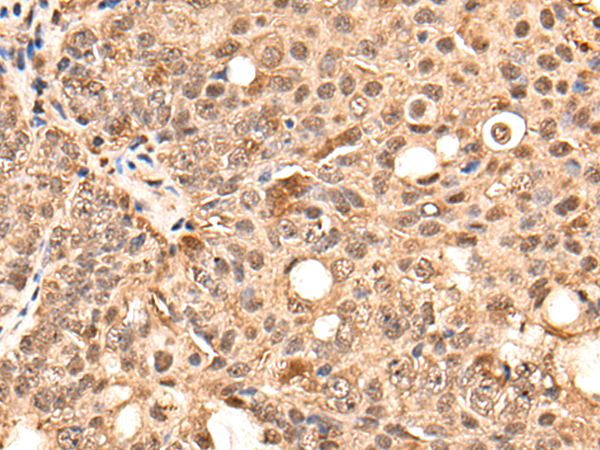

IHC positive control: |

Human ovarian cancer and human gastric cancer |

IHC Recommend dilution: |

25-100 |